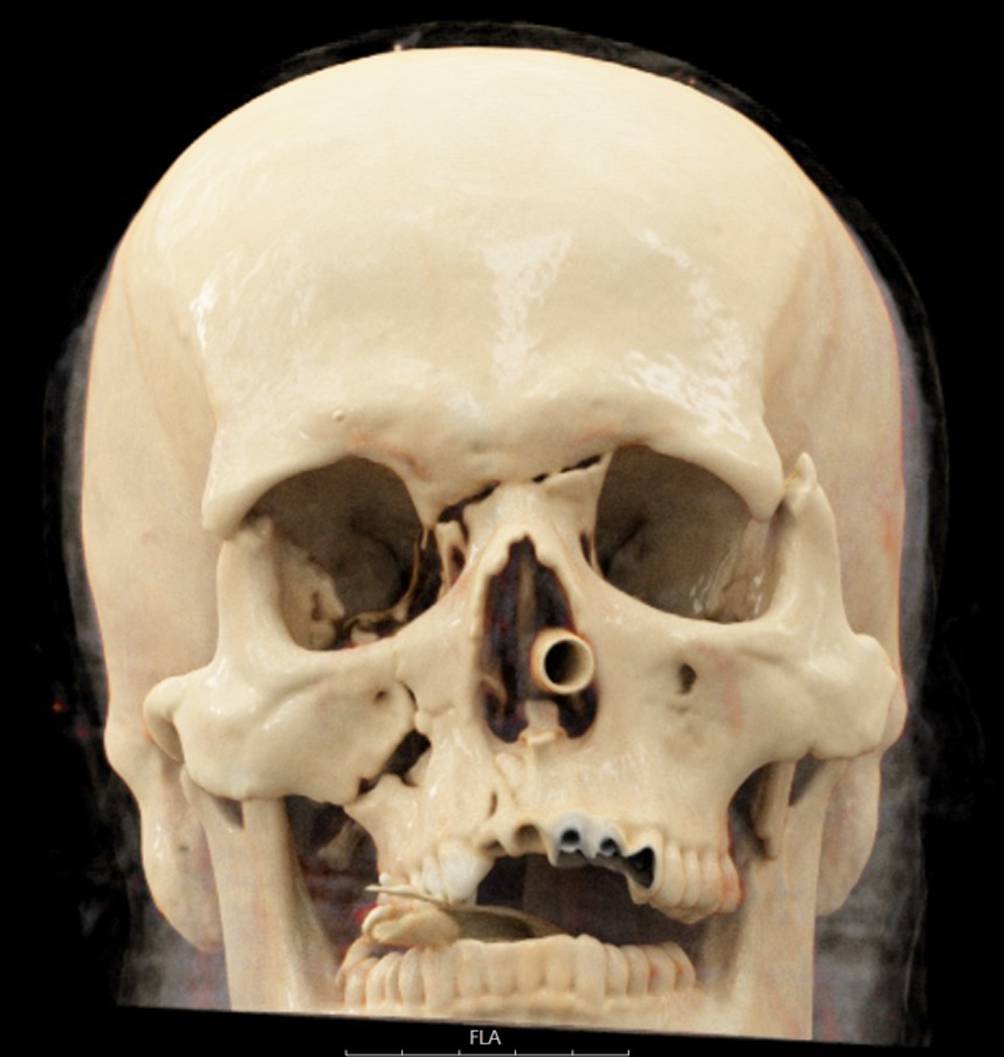

Abb. 2

Koronarer Schnitt der initialen computertomographischen Diagnostik im Rahmen der Schockraumversorgung mit Nachweis eines Pneumomediastinums

Bei nun stabiler Kreislaufsituation (ohne Volumen- oder Noradrenalingabe) und gemäß aBGA ausreichender Oxygenierung und Ventilation entschieden wir uns, zunächst einmal auf die Anlage von Thoraxdrainagen zu verzichten und die bildgebende Diagnostik durch eine Computertomographie (CT) zu vervollständigen. Diese zeigte im Wesentlichen komplexe Mittelgesichtsfrakturen (LeFort-I-Fraktur rechts komplett, links inkomplett, LeFort-II-Fraktur rechts und LeFort-III-Fraktur beidseits, Abb. 1), nichtdislozierte Frakturen der Processi transversi des Halswirbelkörpers (HWK) 7 und der Processi transversi der Brustwirbelkörper (BWK) 1 und 2 rechts, einen schmalen beidseitigen Hämatopneumothorax mit maximaler Saumbreite von 2,5 cm, Rippenserienfrakturen beidseits (Costae I–VII rechts, Costae I–IX links) mit Flail-Segment rechts (Costae I–VII jeweils mehrfach zwei- oder dreifach frakturiert), eine Lungenkontusion und -lazeration beidseits sowie ein Pneumomediastinum (Abb. 2). Bis auf die genannten Querfortsatzfrakturen fand sich keine weitere Wirbelsäulenverletzung, das Alignment war über die komplette Wirbelsäule intakt.

Aufgrund des nachgewiesenen Pneumomediastinums wurde unmittelbar nach Abschluss der CT-Diagnostik noch im Schockraum eine Bronchoskopie durchgeführt. Dabei zeigte sich dorsal auf Höhe der Carina eine etwa 3 cm lange Trachealruptur, die sich spiralförmig bis in den rechten Hauptbronchus erstreckte (Abb. 3). Die Tubusspitze lag 5,5 cm kranial von der Carina. Die nun bronchoskopisch diagnostizierte tracheobronchiale Ruptur ließ sich retrospektiv auch in den CT-Bildern verifizieren (Abb. 4). Somit bestand die dringende Op.-Indikation zur Übernähung der Trachea über eine rechtsseitige Thorakotomie. Noch im Schockraum vor Verlegung in den OP wurde linksseitig eine Thoraxdrainage in Bülau-Position eingelegt, bei unmittelbar folgender Thorakotomie rechts und aktuell tolerierbarer kardiopulmonaler Situation verzichteten wir zunächst auf eine Drainage-Anlage rechts. Durch die Kollegen der Gastroenterologie wurde noch vor Verlegung in den OP endoskopisch eine Begleitverletzung des Ösophagus ausgeschlossen. Auf eine präoperative magnetresonanztomographische Darstellung (MRI) der spinalen Achse bei bis dahin nicht erklärter peripherer Plegie der Beine und des rechten Arms wurde aufgrund der zeitdringlichen thoraxchirurgischen Op.-Indikation verzichtet.